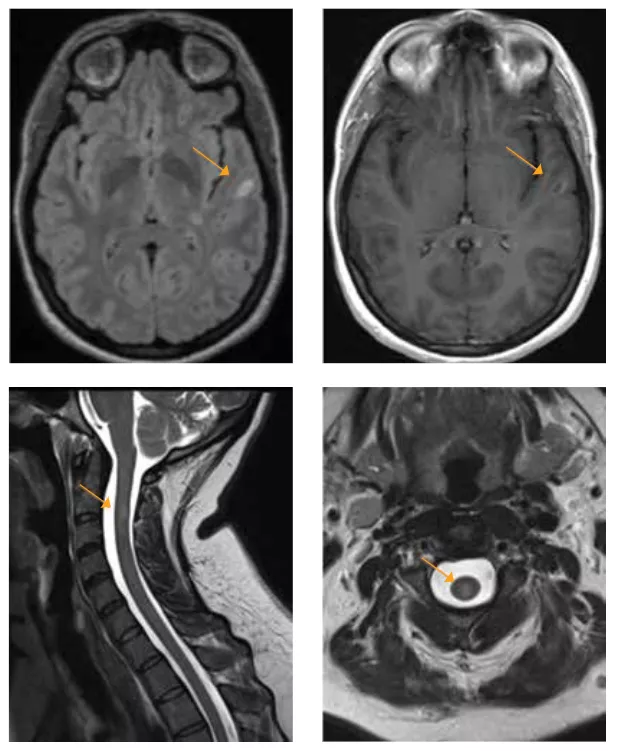

2019 Brain MRI

In 2021, she began to develop numbness in her right arm and hands that progressed over one month to encompass her left arm and hands. She was seen at AdventHealth Neurology in Winter Park and underwent further testing that included MRI of the brain, cervical and thoracic spine. As her previous images were compared to her current images, she was found to have previous lesions in the brain located in the periventricular and infratentorial region of the brain, which are common locations for lesions of MS.

Mizell MS 2

2021 Brain MRI